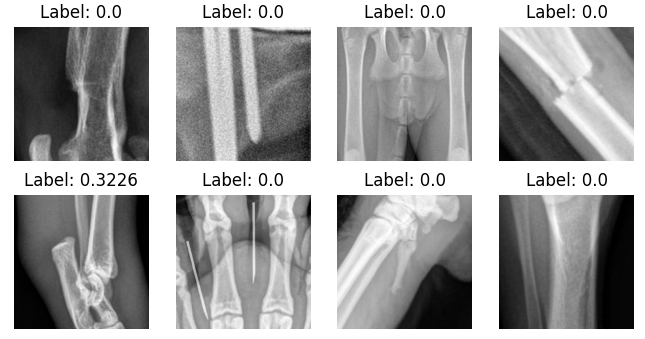

The study utilizes a dataset comprising 3970 veterinary radiology images associated with limb fractures (80/20 train test split). The identification of aberrant predictions is facilitated through the analysis of regions within the images that significantly influence the classifier’s predictions. To further elucidate the framework’s capability in identifying aberrant predictions, two complementary evaluation methods were employed.

Saliency-map-crop evaluation The saliency maps were initially evaluated using fracture mask bounding box labels provided by expert veterinarians. The metric we employ, which we refer to as Saliency Crop Accuracy (SCA) is a specialized adaptation of the Intersection over Union (IoU) metric commonly used for object detection tasks [52]. Unlike traditional IoU focusing solely on overlapping areas between predicted and ground-truth bounding boxes, SCA considers the centroids’ distance when no overlap occurs, introducing a decay factor proportional to the inverse of this distance. A high SCA value indicates a likely accurate prediction, while a zero value signifies misdirection in the saliency map. This evaluation suggests that all aberrant predictions will exhibit a very low saliency map accuracy metric value, which serves as a quantifiable measure of the aberrance of the predictions.

Visual inspection However, the saliency map metric alone may not capture the complete picture, especially in scenarios where reasonable-looking regions did not contain a fracture (i.e. the SCA will be low, but the prediction is not aberrant). To address this limitation, a visual inspection of the predictions in each scenario was carried out. This dual-method evaluation motivates a more holistic approach to understanding ‘accuracy’, emphasizing the importance of not only examining the alignment between the saliency maps and ground truth but also scrutinizing the logical coherence of the identified regions.